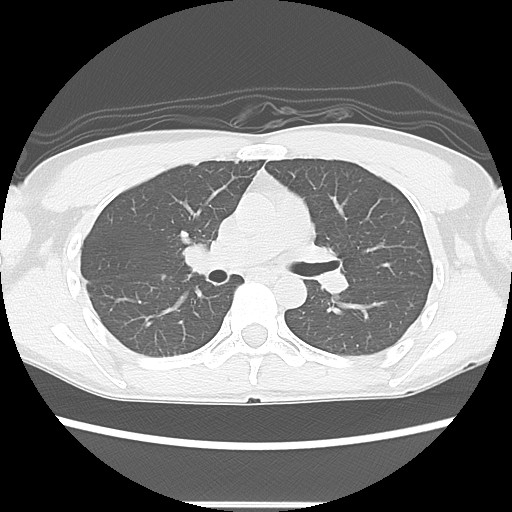

相変わらず0.1でギリ陽性を維持。 まあ上がらず横ばいなのでOKだな。 先生も全く気にしていない様子。 とはいえ「次回は9月にCTと採血ね」と抜かりなし(笑)。 2/16に採血とCT撮影をしてきた。 【4月】 時間厳守で8:15頃に核医学科を受付。 更衣室に案内されて着替え。 ロッカー開けてスリッパを見て一人爆笑(笑)。 誰もいないのでスリッパの写真を撮る。 続いて検査手順の説明を受ける。 ・投薬 ・1時間休憩 ・水分はたくさん摂ってください ・20分撮影 ・30分休憩 ・誰にも何も言わずそのまま帰ってよし とのこと。 そして静注用のライン取り。 血管が細く看護婦も悩み、少々時間を使う。 でも慎重に血管を選び抜き一発でライン確保。 さすがである。 血管にラインが入っている感覚、一瞬で抗がん剤治療時の腕の感覚が蘇るから不思議だ。 そしていきなり1時間休憩。 何も持ち込みできないので、ただただボ~ッとする。 これにも理由があって、筋肉を使うとそこに薬剤が集まってしまうらしい。 だから「何もしない」でなければならない。(と帰宅後にヨメから教わる) 体内というか細胞に薬剤が行き渡ったら20分ほどかけて撮影。 CTの機械を少々長くした程度のものだった。 気分的にもCTと同じ。 体勢は腕を横にしてきをつけの姿勢。 いつもは万歳の姿勢なので少し画像が変わりそうだ。 撮影後は30分休憩。 こちらは半減期との兼ね合いのようだ。 俺自身が放射線を出しながら街中を歩いて電車に乗るわけにはいかないということかな。 γ線エリアモニタなるものも所々に設置されている。 空間線量を計測している模様。 俺が近づいただけで0.1から12.0までどんどん上昇した。 俺自身が放射線を出しているということで、ちょっとおもしろい(笑)。 というわけで、本来であれば悪性腫瘍を疑われての検査なのだけど、あまりにも経験したことのないことばかりで、逆に楽しんでしまった(笑)。 結果は12/16。 これまたどんな画像が出てくるのかが楽しみ。